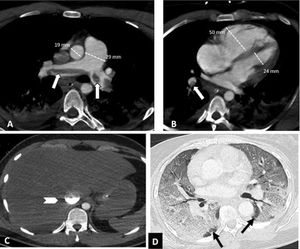

Depending on the location of the most proximal filling defect, thromboembolic involvement was classified as: a) proximal, if the most proximal thrombus was located in the trunk of the pulmonary artery or in the main pulmonary arteries (Fig. 1); b) medial, if the material was located in the proximal lobar or segmental arteries (Fig. 2); or c) distal, if the involvement was distal segmental or subsegmental (Fig. 3).17

Central pulmonary thromboembolism with signs of right heart overload in a patient with severe COVID-19. Chest CT angiography. A-C) Knuckle thrombus at the bifurcation of the pulmonary arteries and in the lobar artery of the right lower lobe (white arrows). Signs of right heart overload: pulmonary artery/aorta ratio >1, enlargement of the right heart chambers with straightening of the intraventricular septum and reflux of intravenous contrast into the inferior vena cava (arrow head). D) Severe parenchymal involvement by COVID-19. Ground-glass pattern involving more than 60% of the lung parenchyma. The black arrows point to the intact lung parenchyma in both lower lobes.

The distribution of thromboembolic material was recorded as left, right or bilateral. The presence of vascular signs potentially indicative of right heart overload (dilation of the right heart chambers, straightening of the interventricular septum and reflux of contrast into the inferior vena cava)18 (Fig. 1) and the presence or absence of pleural or pericardial effusion were also assessed. The right heart chambers were measured on a 4-chamber plane, and right ventricular dilation was considered to be present when the right ventricular chamber was larger than the left — that is, when the right/left ventricle ratio exceeded 1.18 Straightening of the interventricular septum was considered to be present with the loss of the normal right convexity thereof.18

Severity of involvement was classified according to extent of lesions in the lung parenchyma as: a) normal: no involvement; b) mild: <30% involvement of the lung parenchyma (Fig. 3); c) moderate: 30–60% involvement (Fig. 2); or d) severe: >60% involvement of the lung parenchyma (Fig. 1).20–24